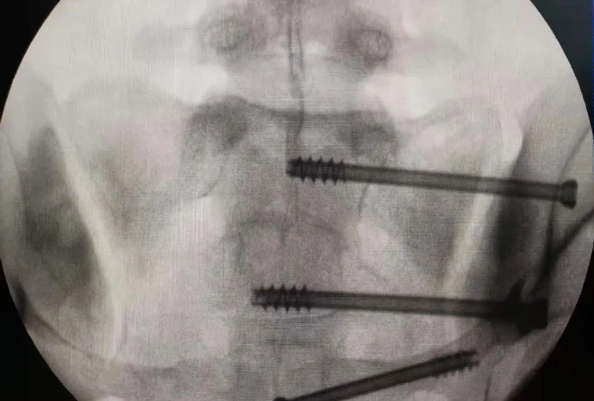

在南昌市第一醫院廖琦教授帶領下,由創傷骨科團隊借助天璣?骨科手術機器人為患者“量身定做”最理想、最安全的教科書般的通道,完美安全微創完成手術,并且手術時間明顯縮短,真正做到“指哪兒打哪兒”!更讓患者放心的是,天璣?骨科手術機器人的“穩定手”機械臂進行精準定位,不用反復探尋。

由于天璣?骨科手術機器人的精準及高效,可以使手術時間明顯縮短,因此在骨盆骨折手術后,在廖琦教授指導下,脊柱外科團隊利用天璣?骨科手術機器人同樣為20歲女性腰椎骨折患者“量身定做”最理想、最安全的教科書般的通道,完美安全微創完成手術,手術不僅時間縮短,并且出血和透視減少。